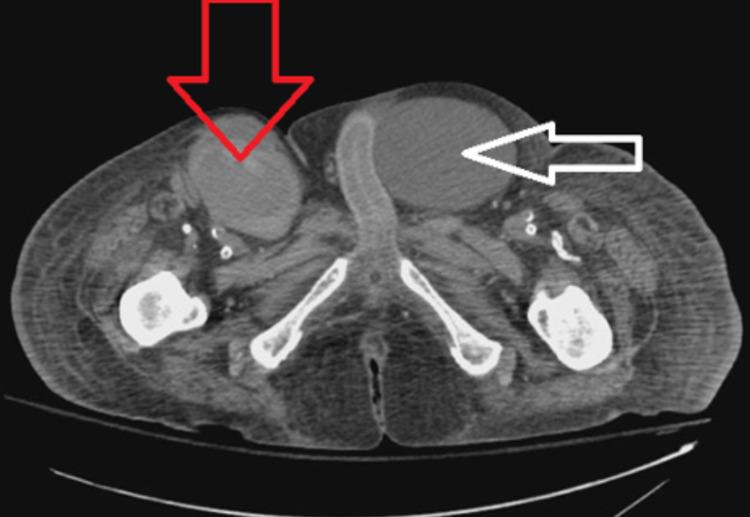

Femoral artery pseudoaneurysms have an increased incidence over the past few years due to the rise in percutaneous catheterization and so have the potential treatment options. Ultrasound-guided thrombin injection has been strongly studied, and data have shown its efficacy, safety, and superiority to ultrasound-guided compression therapy as well as open surgical repair; however, a less well-studied approach that appears to be burgeoning is endovascular stent repair. Many small studies and case reports have shown this option to be not only effective but also safe and might be the treatment option of choice in patients who are deemed high risk for surgical intervention or with complicated anatomical considerations at the site of injury. In this case report, we describe a 71-year-old man with an expanding right groin hematoma which was discovered to be a right superficial femoral artery pseudoaneurysm with a venous fistula connection to the common femoral vein. Due to the patient's venous fistula component, high surgical risk from substantial comorbidities, and large pseudoaneurysm size with a wide pseudoaneurysm neck, thrombin injection, compression therapy, and open surgical repair were ruled out as potential treatments; therefore, endovascular stent repair was performed. The procedure was successful, as was the patient's postoperative period. This case report and literary review can support and further validate the usage of endovascular stent repair to treat femoral artery pseudoaneurysms.

在过去几年中,由于经皮导管插入术的增加,股动脉假性动脉瘤的发病率有所上升,其潜在的治疗选择也随之增加。超声引导下注射凝血酶已得到深入研究,数据表明其有效性、安全性以及相较于超声引导下压迫疗法和开放手术修复的优越性;然而,一种似乎正在兴起但研究较少的方法是血管内支架修复。许多小型研究和病例报告表明,这种选择不仅有效,而且安全,对于那些被认为手术干预风险高或损伤部位存在复杂解剖学因素的患者而言,可能是首选的治疗方法。在本病例报告中,我们描述了一名71岁男性,其右侧腹股沟血肿不断扩大,经检查发现是右侧股浅动脉假性动脉瘤,并与股总静脉存在静脉瘘连接。由于患者存在静脉瘘成分、大量合并症导致的高手术风险以及假性动脉瘤尺寸较大且假性动脉瘤颈部较宽,凝血酶注射、压迫疗法和开放手术修复均被排除作为潜在治疗方法;因此,实施了血管内支架修复。手术成功,患者术后恢复良好。本病例报告及文献综述可为血管内支架修复治疗股动脉假性动脉瘤的应用提供支持并进一步验证。